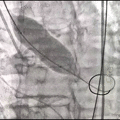

球囊预扩

定位胶囊腔

第一次瓣膜释放

回收再次定位

造影确定瓣膜形态

第二次瓣膜释放

瓣膜释放完毕

术后造影及超声探查未见瓣周漏,跨瓣压差术前44mmHg,术后几乎无压差,术中及术后未出现相关并发症,手术圆满完成。